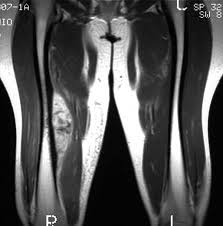

Discrepancia de miembros inferiores en artroplastia total de rodilla. ¿Es realmente un problema?

La incidencia de discrepancia de longitud de miembro inferior tras el con reemplazo total de rodilla fue del 30%. No se requirió  intervención como consecuencia de dicha discrepancia. Los resultados funcionales y dolor al seguimiento alejado no demostraron diferencias entre ambos grupos. Rev Fac Cien Med Univ Nac Cordoba , 16 de septiembre de 2022